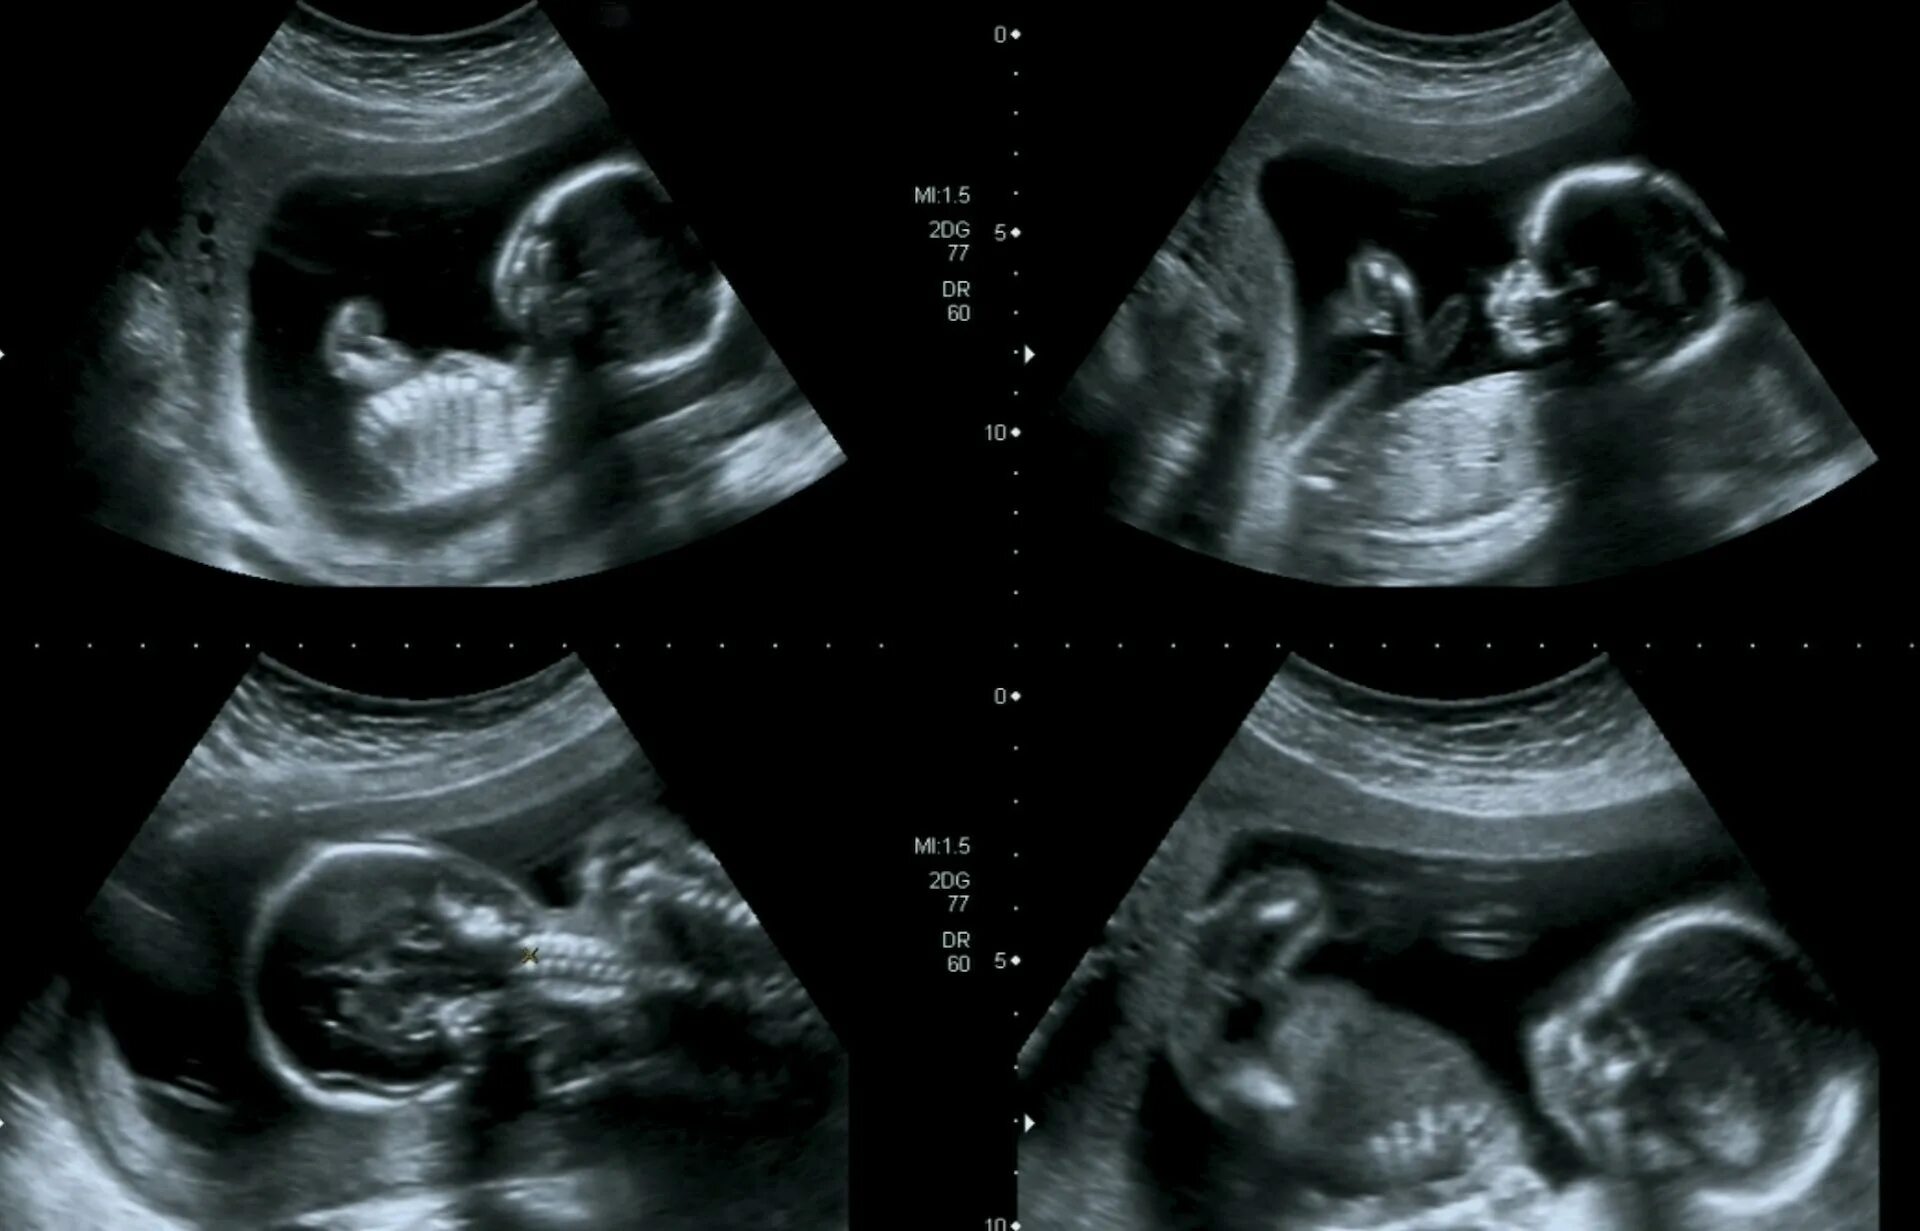

18 недель как выглядит малыш